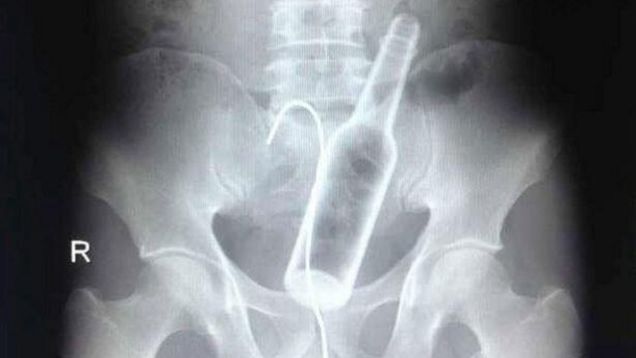

X-rays released by the hospital in Fuzhou, China, show both the bottle and the curved wire used by the man in an wildly ill-conceived attempt to retrieve the bottle.